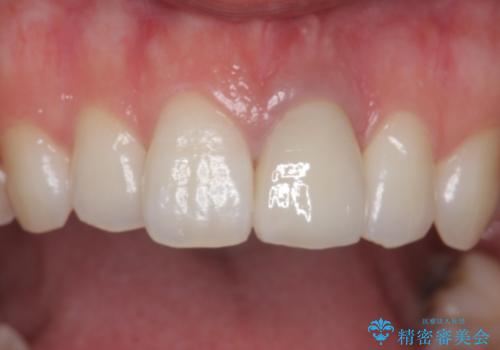

周囲の歯との色調に調和した審美的なクラウンを装着することができました。

歯茎の状態も良く、とても良い仕上がりになりました。